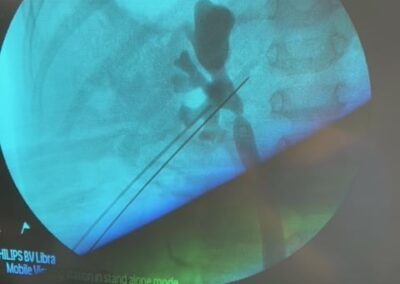

Ο Δρ. Βασίλης Πουλάκης ήταν πάλι όπως κάθε μήνα και τον μήνα Μάρτιο για δύο ημέρες (Δευτέρα 22 και Τρίτη 23 Μαρτίου 2021) στο Ιπποκράτειο Νοσοκομείο στη Λευκωσία της Κύπρου, όπου πραγματοποίησε τέσσερεις ρομποτικές ριζικές προστατεκτομές με διατήρηση των αγγειονευρωδών δεματιών της στύσης και παράλληλα με εκτεταμένο λεμφαδενικό καθαρισμό αλλά και μία αμφοτερόπλευρη διαδερμική νεφρολιθοτριψία (Ultra-Mini PCNL) σε ένα μικρό αγόρι ηλικίας 3,5 ετών με κοραλλοειδείς λίθους και στους δύο νεφρούς.

Η πρωτοποριακή και μοναδική για τα ουρολογικά χρονικά της Κύπρου εξαιρετικά λεπτεπίλεπτη διαδερμική αφαίρεση των ευμεγέθων λίθων και από τους δύο νεφρούς του μικρού αγοριού με μία μόνο επέμβαση-νάρκωση ήταν απολύτως επιτυχής και ο μικρός ασθενής κατέστη ελεύθερος λίθων (“stone free”).

Για την επιτυχή πορεία αυτής της πολύπλοκης και δύσκολης επέμβασης θα ήθελα να ευχαριστήσω όλους όσους, επώνυμα και ανώνυμα, βοήθησαν αλλά κυρίως τους συνεργάτες μου Ουρολόγους, Βασίλη και Νίκο που με στήριξαν σε κάθε βήμα αυτής της περίπλοκης επέμβασης.Παρακάτω οι φωτογραφίες από την ακτινοσκόπηση την ώρα της επέμβασης και η τελική εικόνα με τις νεφροστομίες.